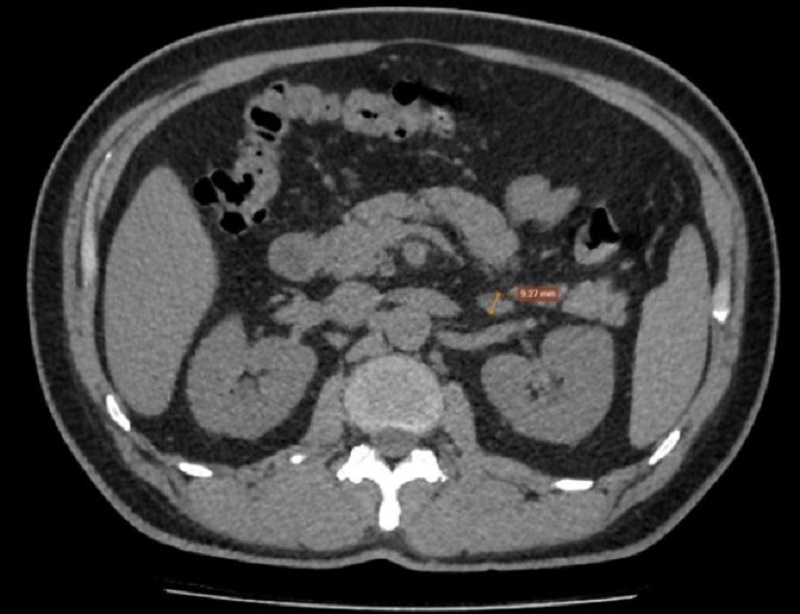

Sau đó, bác sĩ đã chỉ định chụp cắt lớp vi tính tuyến thượng thận. Kết quả chụp tuyến thượng thận: tuyến thượng thận trái tăng kích thước, vị trí lớn nhất dày xấp xỉ 13 mm, không thấy khối rõ ràng - gợi ý tăng sản tuyến thượng thận trái.

Chụp cắt lớp vi tính ổ bụng phát hiện hình ảnh phì đại (tăng sản) tuyến thượng thận trái.

Dựa vào kết quả lâm sàng, xét nghiệm và chẩn đoán hình ảnh, bệnh nhân được chẩn đoán xác định: Cường aldosterone nguyên phát (Hội chứng Conn) - Tăng sản tuyến thượng thận trái.